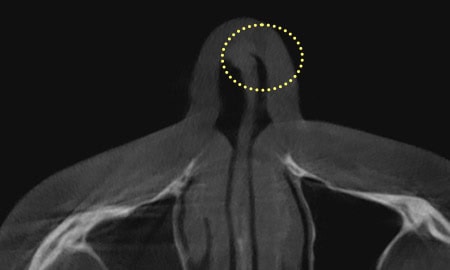

由于肥厚性鼻炎、鼻阀狭窄症、鼻中隔偏曲症等问题

通过去除引发鼻炎、鼻塞、鼻窦炎等功能性障碍的弯曲鼻中隔软骨和骨骼,

将鼻中隔软骨矫正为直线,改善鼻部形态。